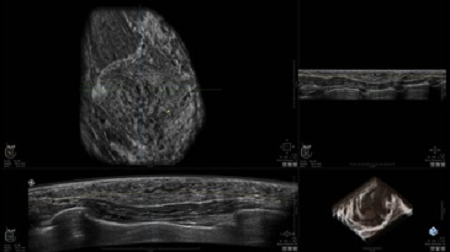

GE INVENIA ABUS – это современный УЗИ аппарат, который создан для точной и эффективной диагностики сканирования с высокой плотностью молочных желез. Выявляемость патологий раковых и предраковых стадий заболевания составляет 55%, что в конечном счете позволяет ставить врачу точные и своевременные диагнозы. Традиционные методы использования маммографии не показывают такой выявляемости, ограничиваясь лишь 3-38%.

УЗИ-аппарат GE INVENIA ABUS позволяет проводить максимально операторонезависимые процедуры, что значительно снижает риск неправильной постановки диагноза и сопутствующие издержки на обработку информации. Система готовит отчет в течение 3-х минут после сканирования, это безусловное преимущество по сравнению с обычным УЗИ сканером.

• Получение объемных 3D изображений с возможностью покадрового просмотра

• Отображение объемных 3D ультразвуковых изображений, которые состоят из традиционных поперечных и воссозданных коронарных и сагиттальных проекций

• Возможность отображения полного 3D изображения

• Стандартизованная ориентация изображения: «толстый срез» в коронарной плоскости; поперечная; сагиттальная плоскость; радиальный и антирадиальный поворот изображения; просмотр исключительно области интереса